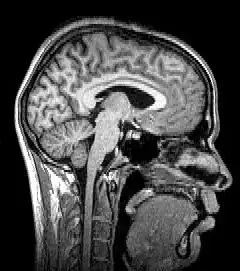

![]() Para-sagittal MRI of the head in a patient with benign familial macrocephaly | |

Magnetic resonance imaging (MRI) uses magnetic fields and radio waves to produce high quality two- or three-dimensional images of brain structures without the use of ionizing radiation (X-rays) or radioactive tracers.